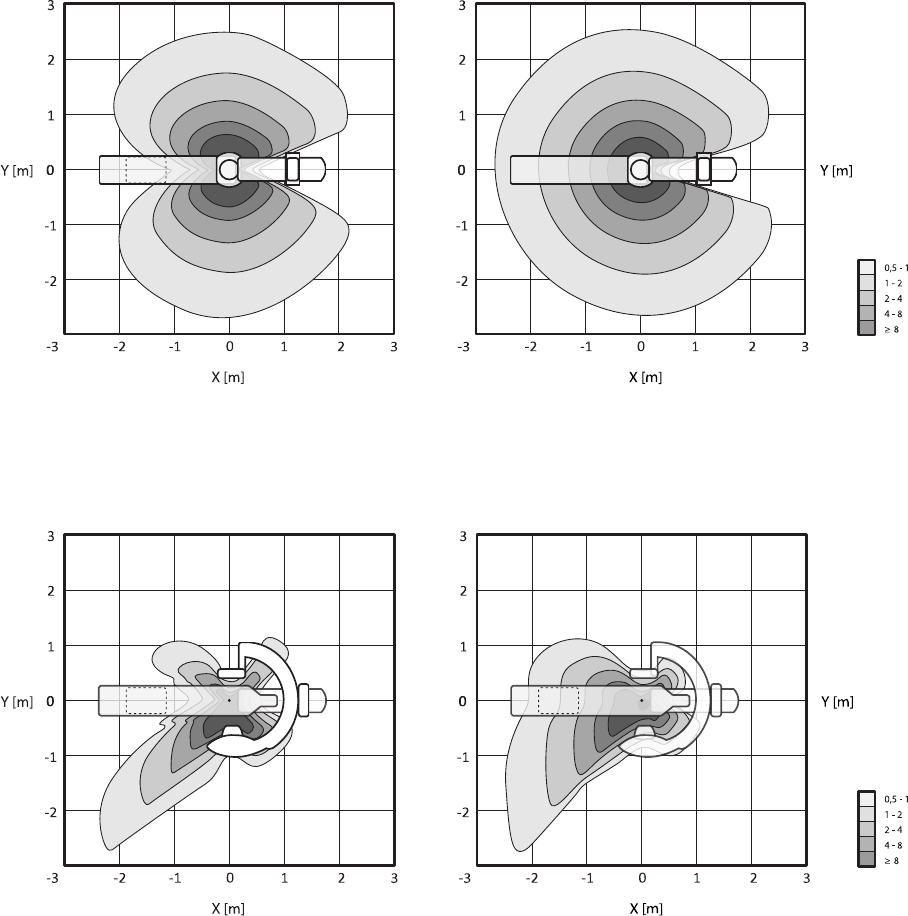

16.21 Ochrona przed promieniowaniem rozproszonym................................................................ 308

16.21.1 Strefa przebywania.............................................................................................. 308

16.21.2 Mapy izokermy systemu C12/F12........................................................................ 310

16.21.3 Mapy izokermy systemu F15................................................................................ 311

16.21.4 Mapy izokermy systemu C20/F20........................................................................ 312